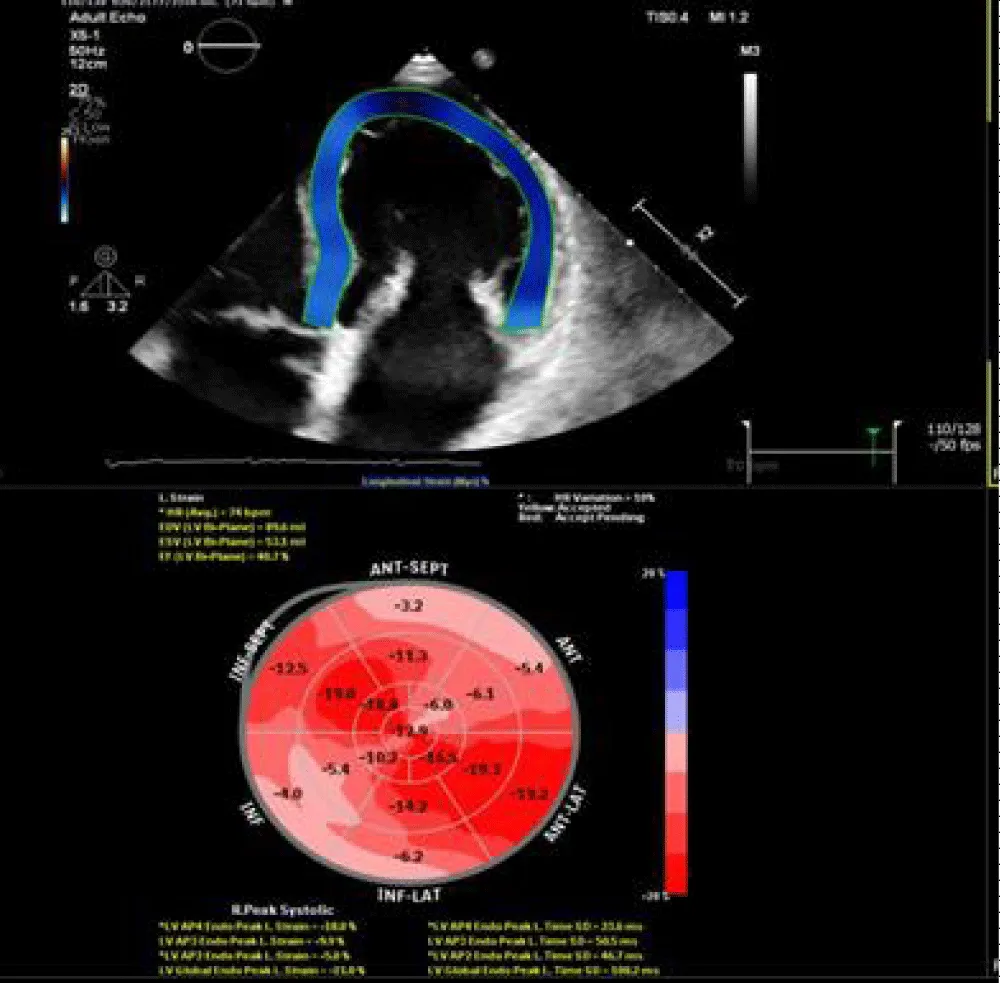

Case 2 mitral annulus disjunction (MAD) with mitral valve prolapse

25 years old male, presented by palpation. 2D echocardiography revealed MAD with mitral valve prolapse causing moderate to severe mitral regurgitation. Average LV volumes were noted with preserved systolic function, EF = 62 % and GLS = -19.7%. 3D echo revealed average LV volumes with mildly impaired, EF = 52% and mildly impaired GLS = -17.2%. CMR showed average LV with preserved LV systolic function, EF = 64% and impaired GLS = -13.1%. Nonterritorial subendocardial fibrosis was noted affecting the mid-segment of inferolateral and anterolateral walls (Figures 6-11).

Figure 9: 3D TTE revealed average LV volumes with GLS =-17.2%.

Figure 11: Feature tracking revealed impaired GLS = -13.1%.